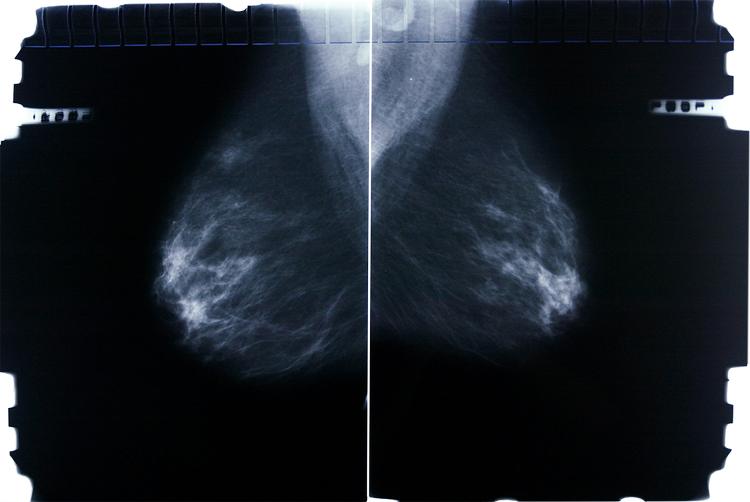

Many women fear developing breast cancer as a result of hormone therapy during menopause. This fear largely stems from a widely-publicized American study from 2002, which later proved to be flawed. Specifically, the risk of breast cancer increases from 10 percent to 11-12 percent after five years of treatment with estrogen and gestagen/progesterone in women over 50 at the start of treatment.